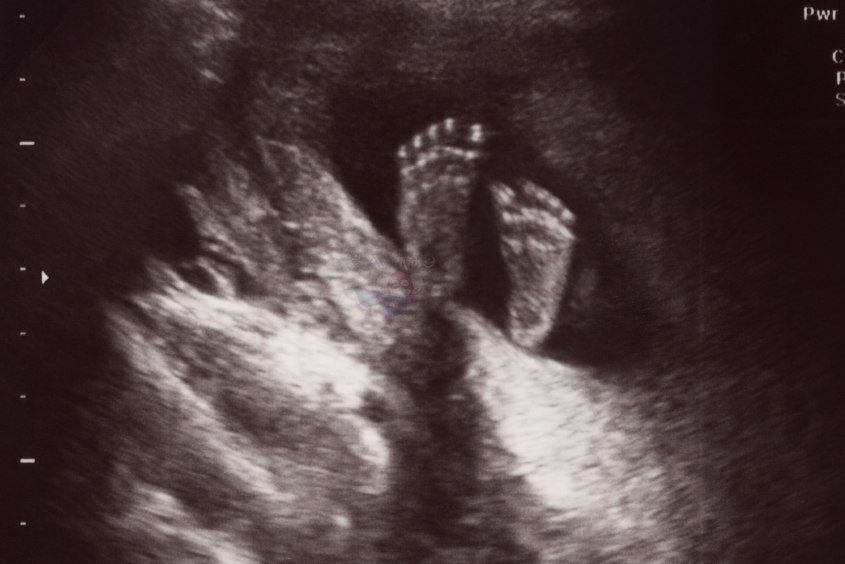

Chiều dài bàn chân của em bé là chiều dài dài nhất tính theo trục dài của bàn chân. Chỉ số này được đo từ đầu sau cùng của bàn chân đế cuối ngón chân thứ nhất hoặc thứ 2, phụ thuộc vào ngón chân nào của bé dài hơn.

Hiện nay chưa có quá nhiều báo cáo về mối tương quan giữa các thông số trong giai đoạn đầu thai kỳ với chiều dài bàn chân thai nhi. Tuy nhiên, các thông tin này vẫn cực kỳ có ích, giúp bác sĩ chẩn đoán được các bất thường của em bé ở những tháng đầu của thai kỳ nếu có.

Đặc biệt, siêu âm chiều dài bàn chân em bé còn có thể giúp mẹ dự đoán được tuổi thai.

Theo các chuyên gia, chiều dài bàn chân có thể bị ảnh hưởng bởi trạng thái tăng trưởng hay sự hạn chế tăng trưởng của thai nhi. Tuy rằng chiều dài bàn chân sẽ giúp mẹ xác định tuổi thai nhưng mẹ cũng cần hiểu rõ các hạn chế của phương pháp này, đặc biệt là đối với những thai nhi có sự tăng trưởng bất thường.

Các chuyên gia cho biết, các chỉ số như đường kính lưỡng đỉnh, chu vi vòng bụng, vòng đầu, chiều dài mông, chiều dài xương đùi đều có mối quan hệ tương quan với chiều dài bàn chân thai nhi. Cụ thể, tương quan tuyến tính sẽ ngày càng tăng khi thai được từ 10 tuần - 16 tuần tuổi.

Mặc dù có thể tính tuổi thai bằng phương pháp siêu âm thai, nhưng vẫn có thể sử dụng chiều dài bàn chân của thai nhi để ước tính chính xác tuổi thai. Tỷ lệ giữa xương đùi và chiều dài bàn chân sẽ giúp mẹ phân biệt thai nhi bị ngắn chi do chậm phát triển hay liên quan tới yếu tố thể chất, loạn sản.